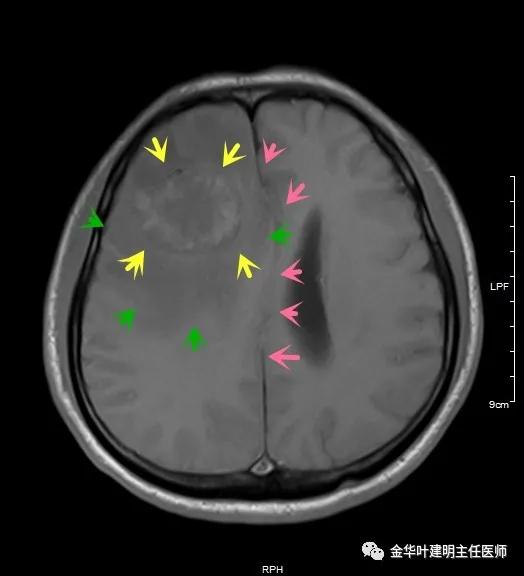

以上图示术前头颅MRI的图像,病灶明显,伴周围显著水肿,中线结构移位。基本可认为是肺癌伴脑转移。那么怎么治疗呢?需不需要手术?能不能手术?手术怎么做?先开颅还是先开肺?